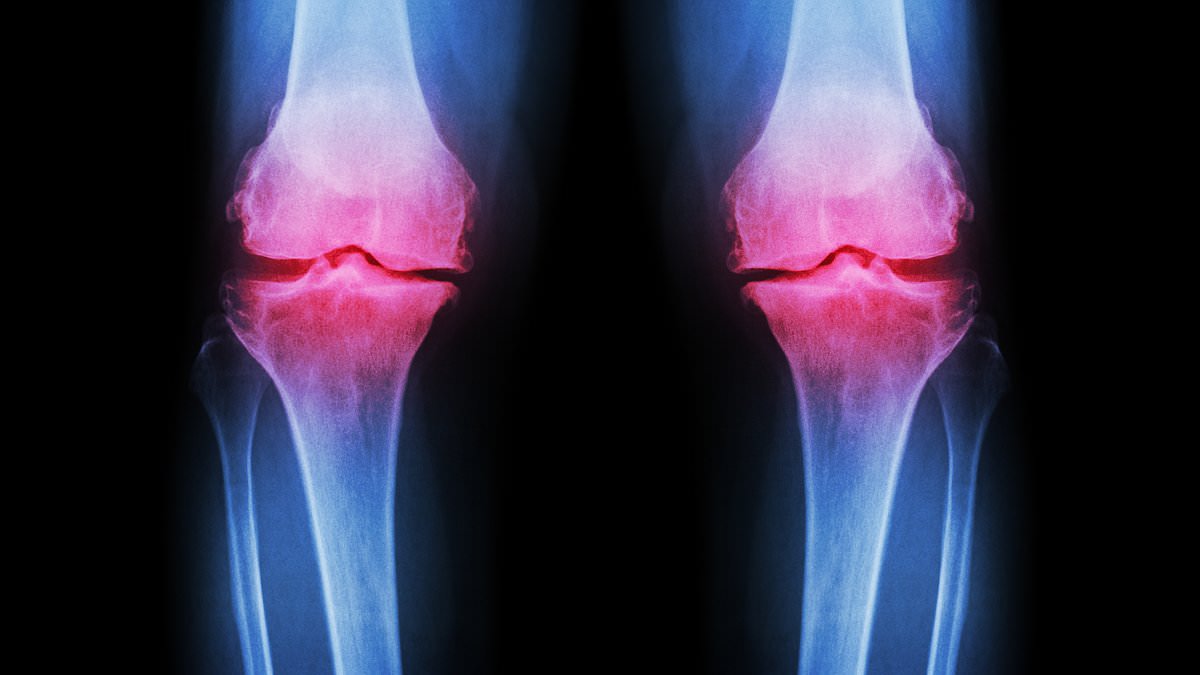

Tim Sinnett, a senior trauma and orthopaedic consultant, highlights the alarming rise in stress fractures, tendon injuries, and advanced cartilage damage among younger patients. 'We're seeing more severe soft tissue injuries around joints due to extreme exercise,' he explains. 'Cartilage breakdown is no longer confined to older adults—this is happening in people in their 20s and 30s.' By age 70, about half of the population will develop osteoarthritis, but the condition is now appearing decades earlier, particularly in those who overtrain or follow unscientific nutrition plans.

Osteoarthritis occurs when protective cartilage erodes, leading to joint pain and stiffness. While factors like genetics, obesity, and injury contribute, the role of high-impact fitness and poor nutrition is becoming clear. Post-traumatic osteoarthritis, often linked to joint fractures, is on the rise, with improper healing altering joint mechanics and accelerating cartilage loss. Younger patients face a dual challenge: managing symptoms over decades and dealing with the social and economic impacts of chronic pain during peak productivity years.